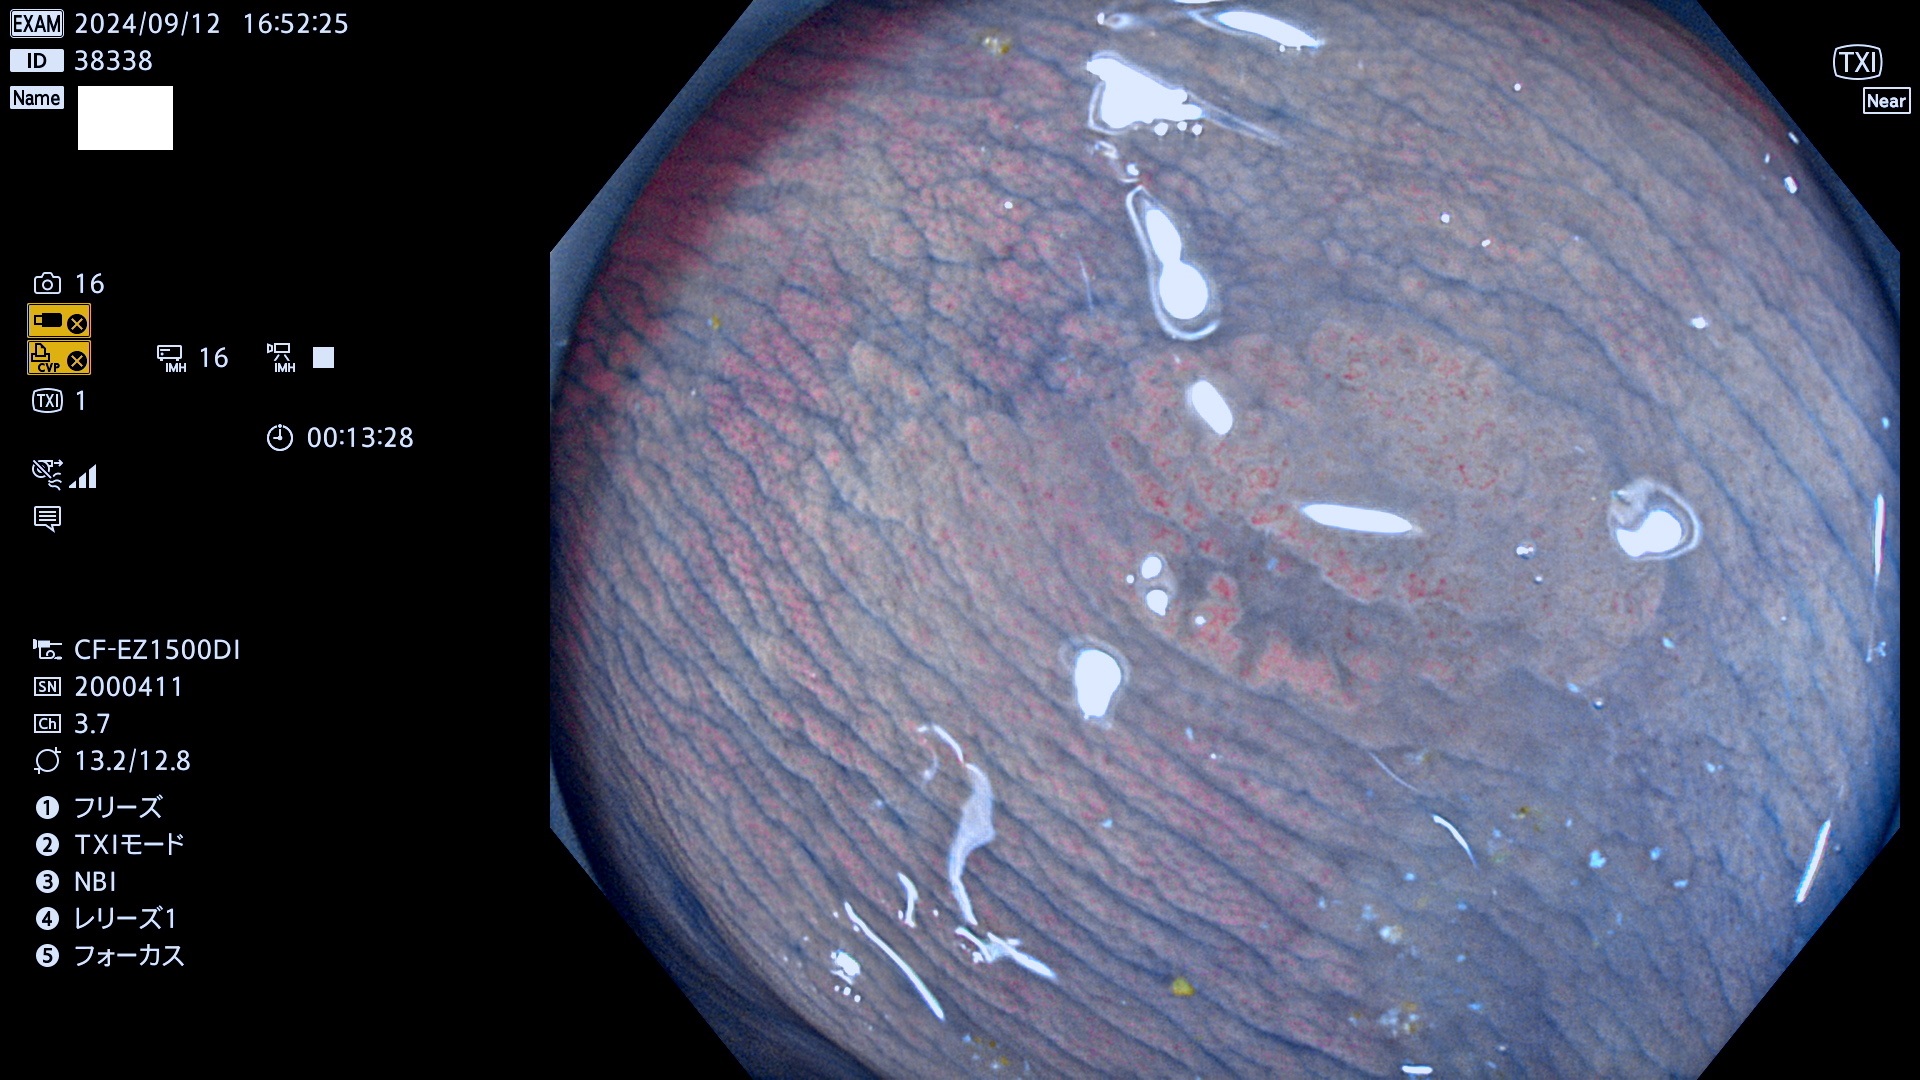

完全に平坦な物をUb、陥凹している物をUcと呼びます。最も発見が難しく危険な病変です。

毎週の検査(木・金・土・日)に発見されたUb、Uc型・腺腫を、その週の日曜の夜にUPし1週間、提示します。

抽出の対象期間 2024年9月12日〜9月15日の4日間(45件の検査)9件 (9/45=20%)